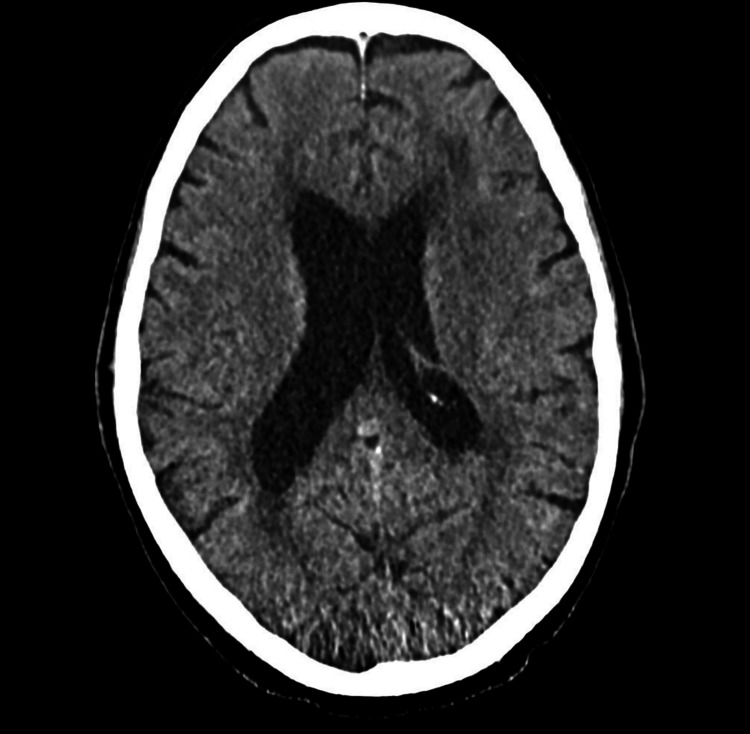

During his most recent admission, a head CT was obtained and was negative for acute disease (Figure 1).